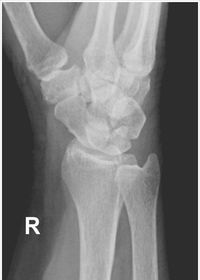

| PA Wrist | wrist externally rotated - joint spaces closed, proximal metacarpals superimposed, carpals superimposed radiocarpal joint is closed |

| PA Wrist | ANATOMY: all carpals including midmetacarpals and distal radius/ulna CRITERIA: true PA is marked by symmetry of proximal metacarpals carpals should be free of superimposition of the metacarpals and radius/ulna POSITIONING: CR perpendicular @ midcarpals |

| Oblique Wrist | ANATOMY: carpals on lateral side of wrist, scaphoid CRITERIA: scaphoid well demonstrated 45 degree obliquity POSITIONING: CR perpendicular @ midcarpals |

| L | CRITERIA: radius/ulna should be superimposed thumb should be forward metacarpals superimposed POSITIONING: CR perpendicular @ midcarpals |